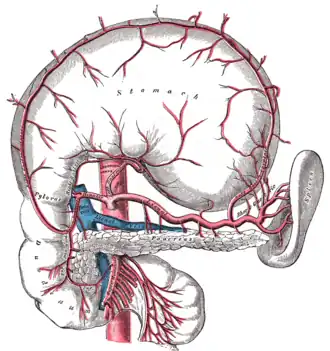

Contrast enhanced MRA of the abdominal aorta demonstrating normal paired arteries.

The celiac artery and its branches; the stomach has been raised and the peritoneum removed.